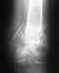

Щейка не срослась. Так что для восстановления безболезненной опороспособности, видимо, придется делать либо эндопротезирование, либо вальгизирующую остеотомию.